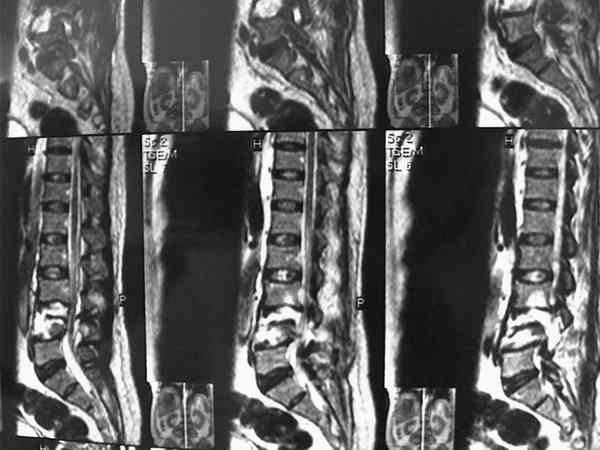

При этой картине удивительно еще то, что у нее нет никаких двигательных и тазовых нарушей.. Жалобы только на боли в спине. Движения и чувствительность в полном объеме. Никаких повреждений сосудистых магистралей также нет. Только изолированный перелом L5 со смещением тела позвонка в мягих тканях (забрюшинном пространстве). Остистый отросток на месте.

В приложении - МРТ.